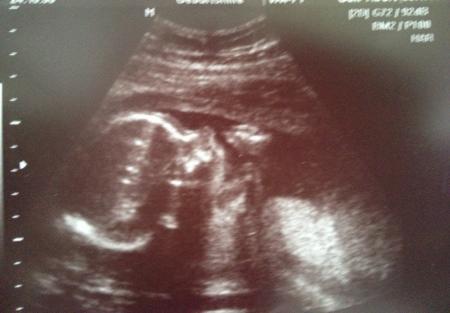

War ja heute auch beim Fa! Organscreening ist alles unauffällig und gesund! Es ist immer noch ein kleiner Prinz! Und er war fleißig am schlafen mim Daumen im Mund!!! Lg

Hab natürlich das Foto vergessen!

Tolles Foto, herzlichen Glückwunsch. So sah ich bei meiner Mama im Bauch auch immer aus :-)